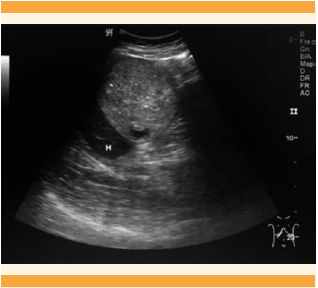

Paciente de 29 años, que acudió al servicio de Urgencias Ginecoobstétricas del Hospital General Dr. Miguel Silva de Morelia, Michoacán, con embarazo de 15.2 semanas (estimado por fecha de la última menstruación) y dolor pélvico agudo de 3 horas de evolución, localizado en la fosa iliaca derecha, que se irradiaba al hipocondrio derecho, incapacitante, calificado en la escala visual análoga de 9. Antecedentes personales patológicos, quirúrgicos, traumáticos, alérgicos, transfusionales y toxicomanías negados. Antecedentes ginecoobstétricos: menarquia a los 14 años, ciclo menstrual 28/4, eumenorreica a expensas de útero gestante; prueba de embarazo positiva; 5 embarazos, 3 partos y 1 aborto. Inicio de la vida sexual activa a los 18 años, una pareja sexual, sin implementación de métodos anticonceptivos; Papanicolaou nunca realizado. Durante la exploración física se encontró con abdomen semigloboso y en la auscultación peristalsis normal. A la palpación media y profunda se percibió resistencia muscular, dolor en la fosa iliaca y hemiabdomen derechos, con signo de rebote positivo en la fosa iliaca derecha; no se palparon visceromegalias ni tumoraciones. A la exploración genital se encontró con cérvix posterior desplazado hacia la izquierda, de consistencia dura, cerrado, dolor a la movilización referido hacia el lado derecho, sin sangrado activo, cavidad vaginal eutérmica. Al tacto bimanual: fondo de saco lateral derecho ocupado por una tumoración de consistencia dura, móvil, doloroso a la movilización, tumoración no delimitada. El ultrasonido abdomino-pélvico reportó un embarazo intrauterino, con feto único, vivo, de 14.2 semanas (estimadas por fetometría), con 140 lpm y placenta normoinserta. También se observó una imagen ovoide, delimitada, de contenido heterogéneo, con imágenes hipodensas en su interior correspondientes a grasa, además de imágenes hiperecogénicas con sombra acústica relacionadas con calcificaciones. A pesar de los hallazgos detectados en el estudio de imagen, no se concluyó la situación anatómica, debido al tamaño de la tumoración y el estado gestacional (Figura 1). La resonancia magnética de abdomen superior evidenció una masa anexial bien definida y delimitada, de bordes regulares, de aproximadamente de 10 x 9 x 9.1 cm, quizá asociada con endometrioma (Figura 2).